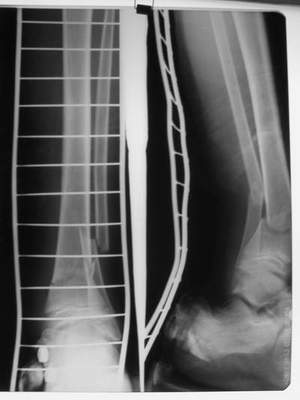

Ребенок 12 лет, поступил после падения с высоты примерно 2,5м.

Перелом костей н\3 правой голени со смещением. Перелом большеберцовой кости можно охарактеризовать как компрессионно-оскольчатый.

Скелетное вытяжение за пяточную кость.

В первые сутки значительный отек с\3, н\3голени, стопы с развитием практически неуловимого в нашей стране ;) компартмент синдрома (фасциотомии не проводилось), недочеты по укладке на скелетном

вытяжении.

Формирование некроза кожи по задней поверхности н\3 голени~ 1 %, вторичное заживление, кожная пластика. Нейропатия м\берцового нерва (отсутствие активного разгибания 1 пальца) На вытяжении около 8 нед, в дальнейшем в гипсовых повязках ~ 8 мес.

Так как речь зашла непосредственно о травме, см этапные

снимки. Как все было

Первичные

Вытяжение